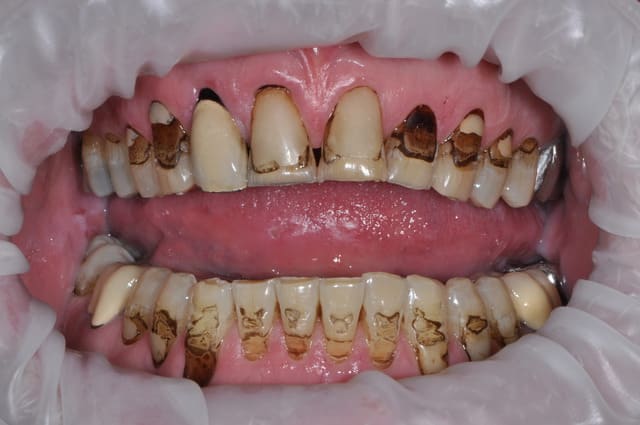

Bonjour,

savez-vous quelle est la raison de cette porosité de surface ?

il s'agit d'emax sur 11 21 22.

Je dirais défaut de cuisson, ça t'explique que les trois couronne sois touché de maniéré homogène, mauvaise porosité qui est passé inaperçus a la pause. Avec les habitues de ton patient (fumeur?), les défauts se remplisse de colorant noir et deviennent évident. Ta pas une grosse fêlure moche sur le milieux de la face vestibulaire de chaque dents?

A priori je dirais trop de cuisson.

La fêlure est certainemnt faite exprès par le prothésiste , il s'agit d'un patient âgé, c'est du maquillage pour faire plus naturel. Pour les porosités je dirais ausi défaut de cuisson

Mauvaise gestion de l'état de surface au labo avant la cristallisation, et voir quel programme de cuisson a été appliqué court ou long.

Moins c'est cuit moins c'est cristallisé

Si l'état de surface est pollué avant glaçage et cuisson on a ce genre de défauts.

si les retouches en phase bleu de métasillicate sont faites avec les mauvaises fraise ou pointe montées....si...

Si la glasure est mal passée.....

ça sent la cuisson sans vide ça .....

non, sortie du four, une ceram n'a pas cet aspect , il n'y a pas de bulles comme ça, soit c'est une infiltration car il a cuit sur du réfractaire et donc l'air est passé au travers ...

sur les Emax, nous nous sommes rendus compte que pour éviter les porosité, il fallait passer la surface à la meule caoutchouc,.

moi je dirais une cuisson glaçage , rajout de céramique de correction avec recouvrement de glasure .. tout en un ..

et paf bubulle ..

je ne pense pas que cet état de surface soit dû à un manque de polissage, que l'emax soit pressé ou usiné ... là il y a des trous qui se remplissent de merde ...

et puis ce ne sont pas des monoblocs non ? c'est donc la partie stratifiée qui déconne .

je penche comme molinarius pour une correction des formes au glaçage mais avec des poudres à la temp de fusion trop élevée pour un glaçage, les "grains" ne ce sont pas suffisamment aggloméré .

je pense que la structure de cette dent n estpas homogene , qu elle est sous cuite ; et que la dent na pas ete degraissee avant glacage le materiau emax est le plus facile a glacer ci joint 2emax 11 12 et deux emax 11 21 merci

Ber la céramique emax est très sensible à la cuisson et très souvent les protho cuisent mal leurs céramique car ils font le programme marqué qu il y est une ou 10 dents dans le four et aussi la position de la dent dans le four est très important donc si la première cuisson est ratée la dent est ratée et souvent sous cuite. Donc porosités !... Et il faut aussi faire attention au glaze ivoclar pour l emax il accentue. Les bulles de surface. Et voilà le résultat.

c'est clair manque de polissage avant glaçage, et la glaz n'a pas été suffisamment appliquée, sur l'Emax faut impérativement effectué un polissage mécanique de surface avant glaçage sinon vous voyez le résultat

L'emax Céram de stratification n'est pas une céramique simple à utiliser.

Les états de surface naturels et exempts de porosités que l'on arrive à obtenir avec les autres céramiques sont réellement moins facilement obtenables avec l'emax.

Tout dépend des programmes utilisés, des liquides de montage, des fraises diamantées, de la glaize, du rapport épaisseur d'armature/épaisseur de cosmétique.

Au final si je reprends les photos de mes premiers cas il y a 6 ans et maintenant l'expérience fait que je n'ai plus de porosités de surface.